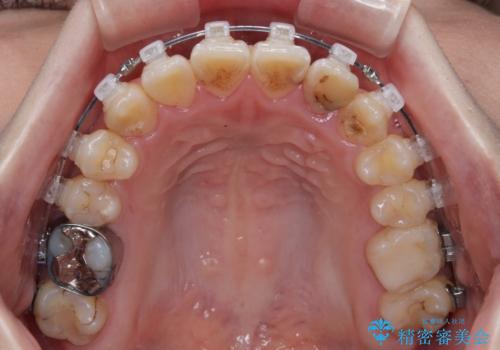

- 矯正装置

- クリアブラケット

急速拡大装置により上顎骨幅を側方に拡大し、それを利用して八重歯を歯列に納めることにしました。